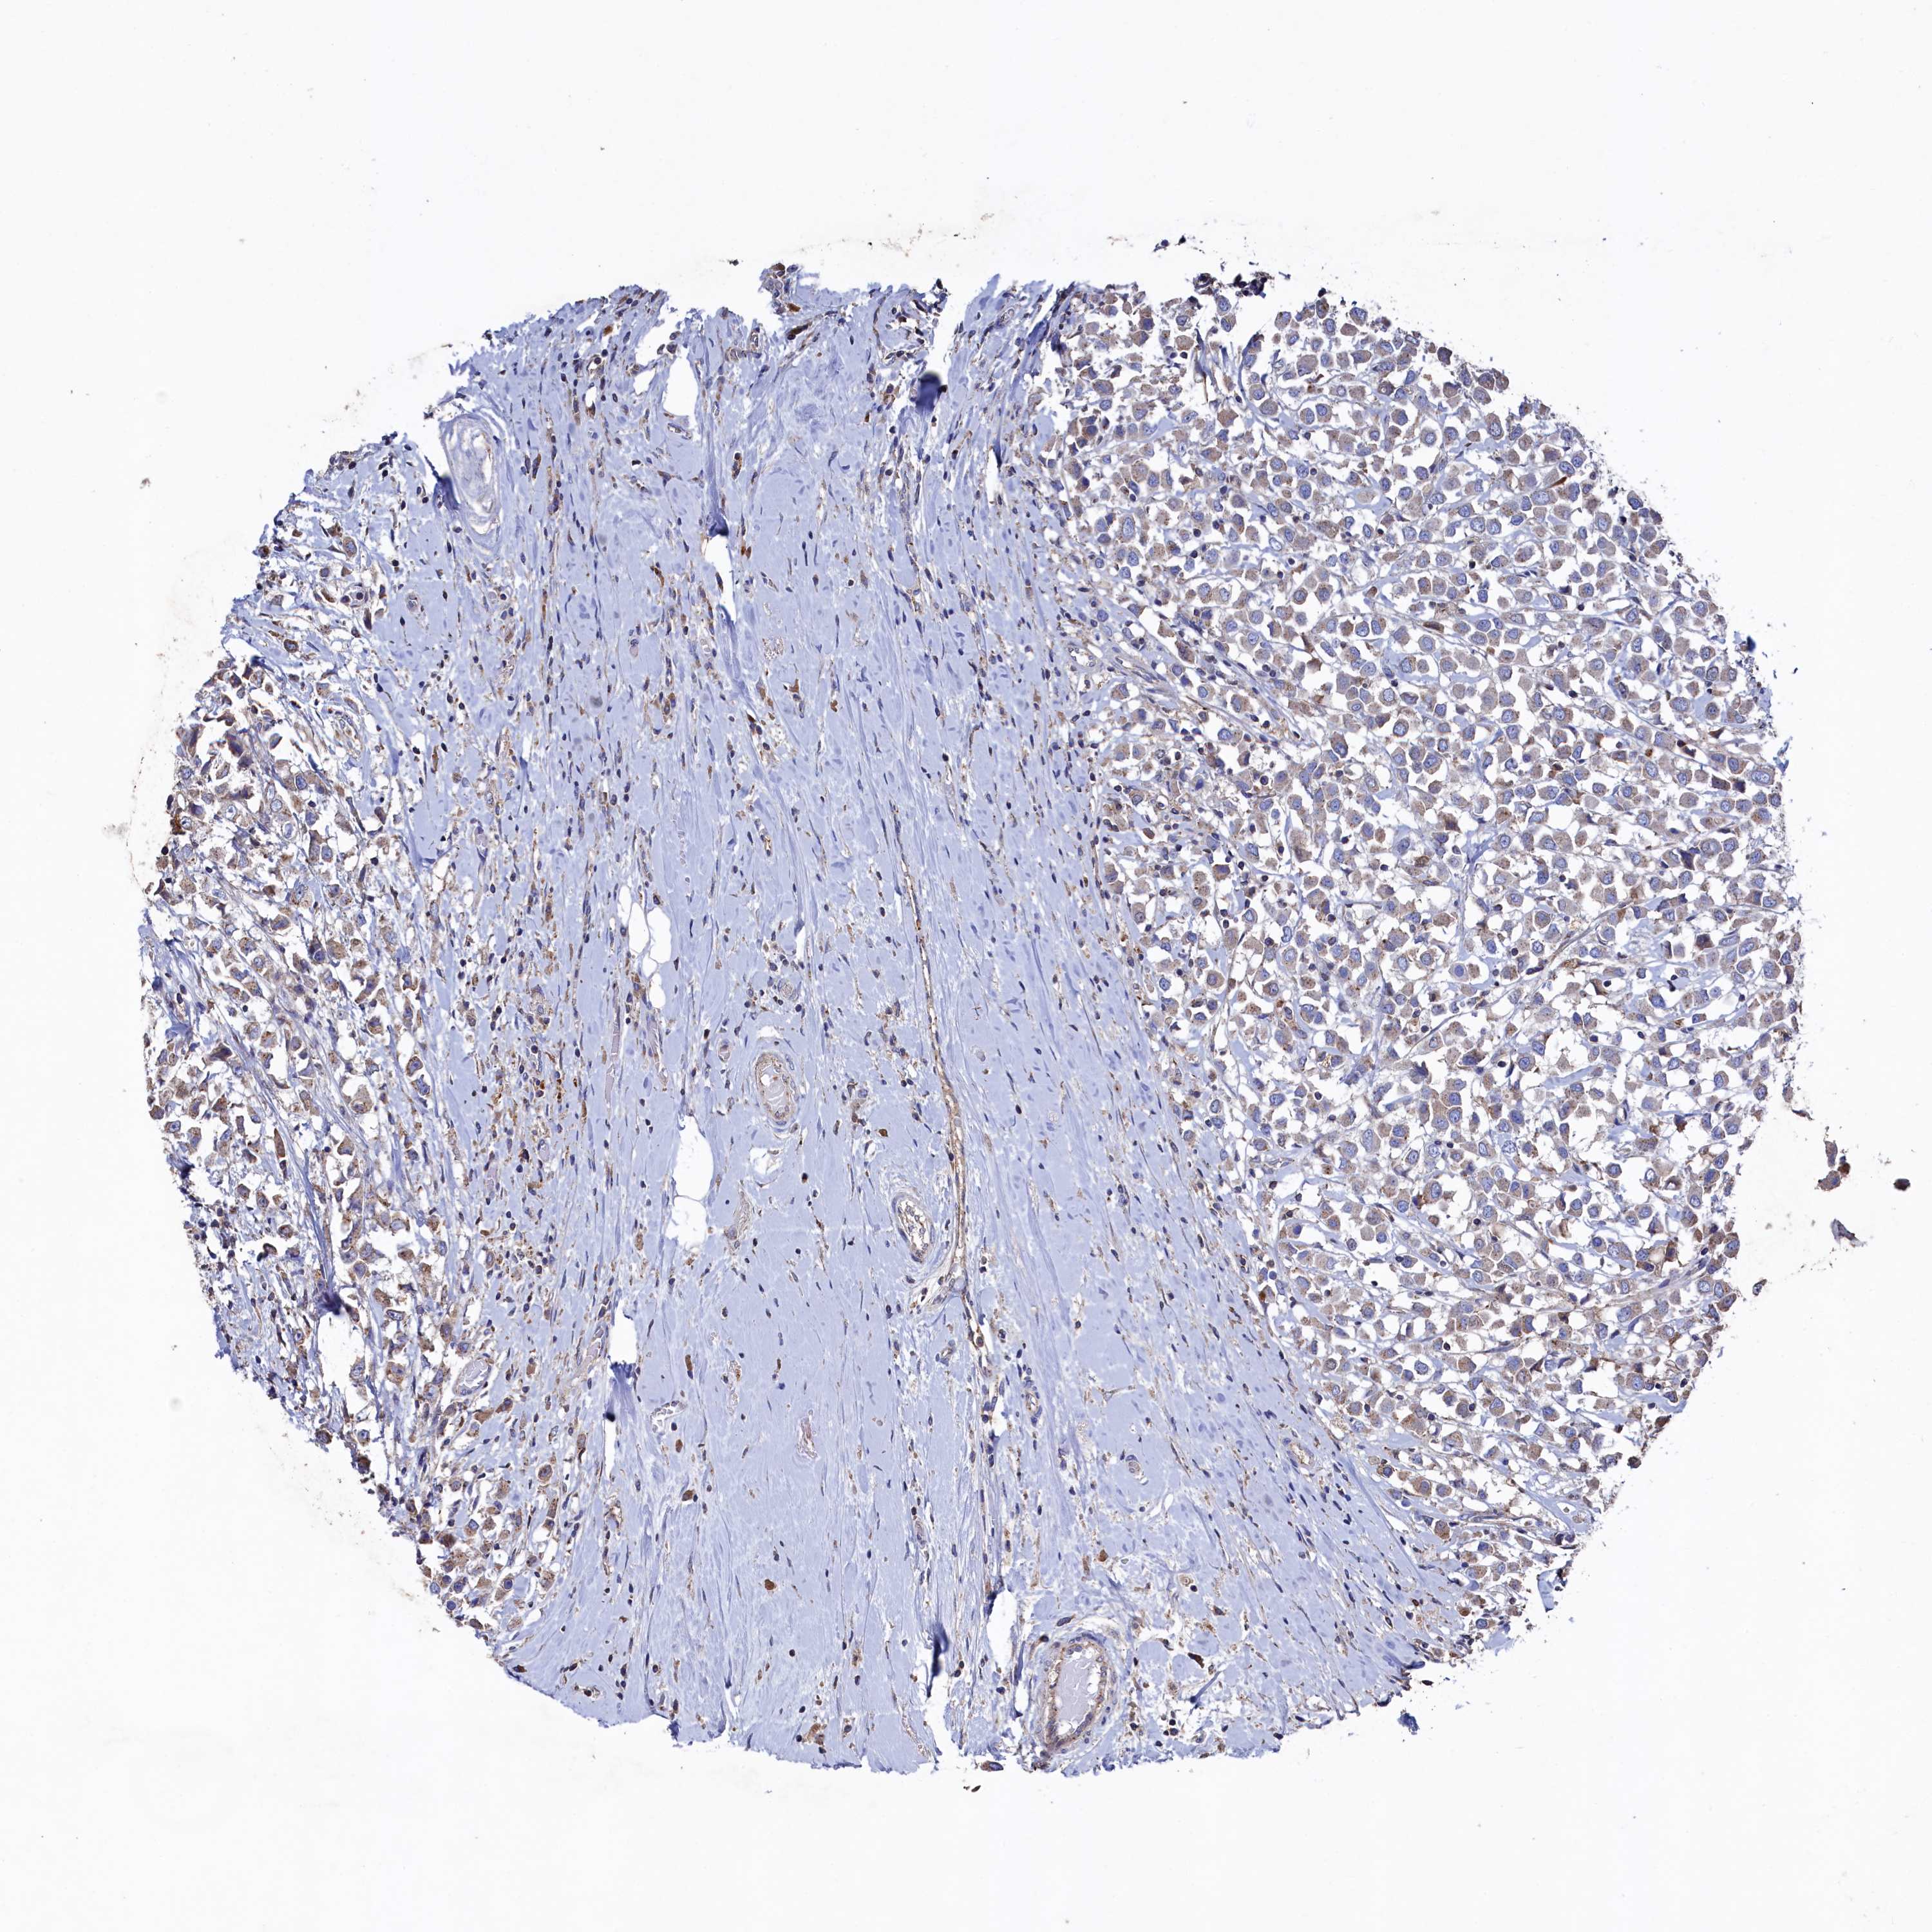

BRCA TCGA BRCA VALIDATION PROTEIN EXPRESSION

ANTIBODIES

AND

VALIDATION